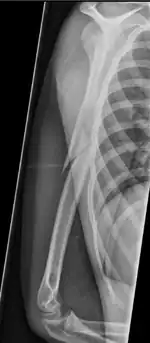

Pathological fracture of the humerus in a patient with metastasis of renal cell carcinoma

Pathological fractures present as a chalkstick fracture in long bones, and appear as a transverse fractures nearly 90 degrees to the long axis of the bone. In a pathological compression fracture of a spinal vertebra fractures will commonly appear to collapse the entire body of vertebra.